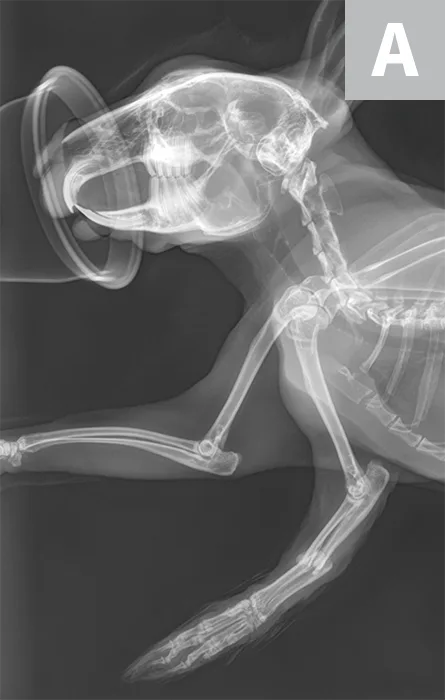

Right lateral radiograph of a 2-year-old male intact rabbit that caught his left front foot in a cage wire; parallel, mid-diaphyseal fractures of the radius and ulna can be seen (A). Due to financial constraints, the pet owners elected for external coaptation, which resulted in frequent splint failure (wet, too tight, pressure sores) that required 3 months of intensive care and resulted in suboptimal bone healing and near loss of the limb due to deep skin infections (B). Ideally, these fractures should have been treated surgically using a bone plate or an extra-skeletal fixation device.